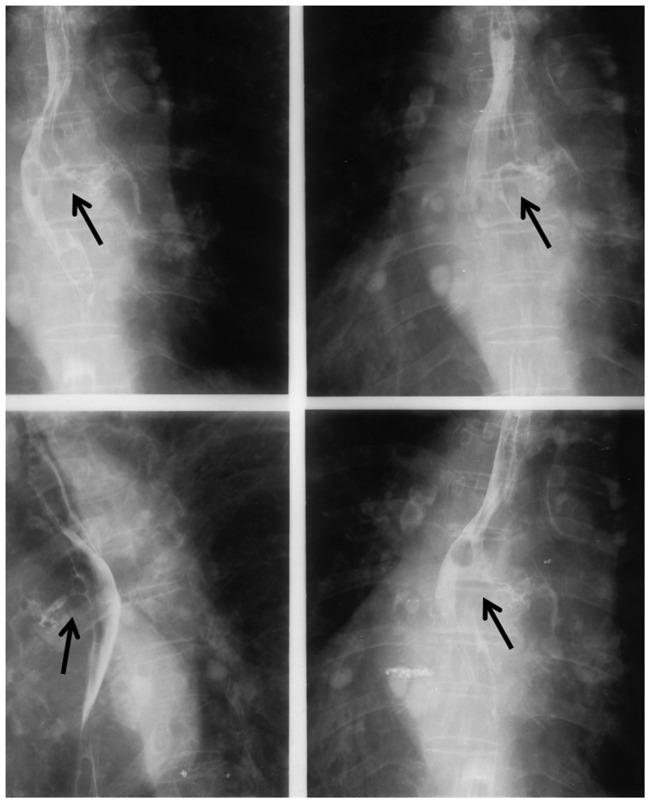

A 76-year-old woman was admitted to the hospital four times from November 2007 to June 2009. In this complex case, the patient had silicosis complicated by broncholithiasis, oesophagobronchial fistulas, and relapsed tuberculosis. She had worked as a stone crusher for 3 years and was exposed to a large amount of quartz dust. Barium oesophagography, gastroesophageal endoscopy, and biopsy suggested oesophageal-related chronic inflammation and ulceration, which may have caused the repeated oesophagobronchial fistulas. Bronchoscopy revealed a free broncholithiasis in the left mainstem bronchus. The patient was admitted a fourth time because of silicotuberculosis relapse. After 9 months of antituberculosis treatment, the patient recovered and was still clinically well at the time of this writing.

一名76岁女性在2007年11月至2009年6月期间4次入院。在这个复杂病例中,患者患有矽肺,并发支气管结石、食管支气管瘘和复发性肺结核。她曾做过3年碎石工,接触过大量石英粉尘。食管钡餐造影、胃食管内镜检查及活检提示食管相关慢性炎症和溃疡,这可能是反复发生食管支气管瘘的原因。支气管镜检查发现左主支气管有一枚游离的支气管结石。患者因矽肺结核复发第4次入院。经过9个月的抗结核治疗,患者康复,在撰写本文时临床状况仍良好。